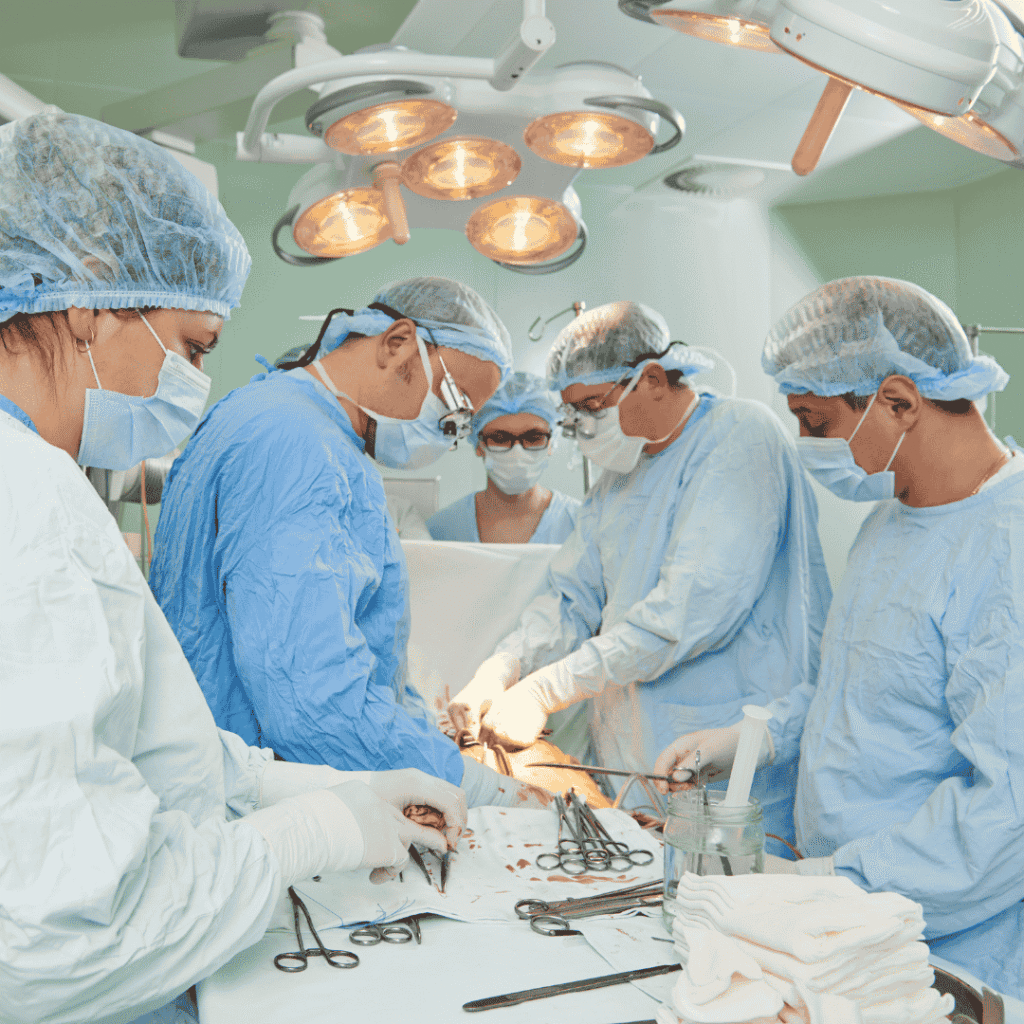

Minimally Invasive Procedure

The pacemaker implantation procedure is minimally invasive, ensuring a quicker recovery and reduced risk of complications.